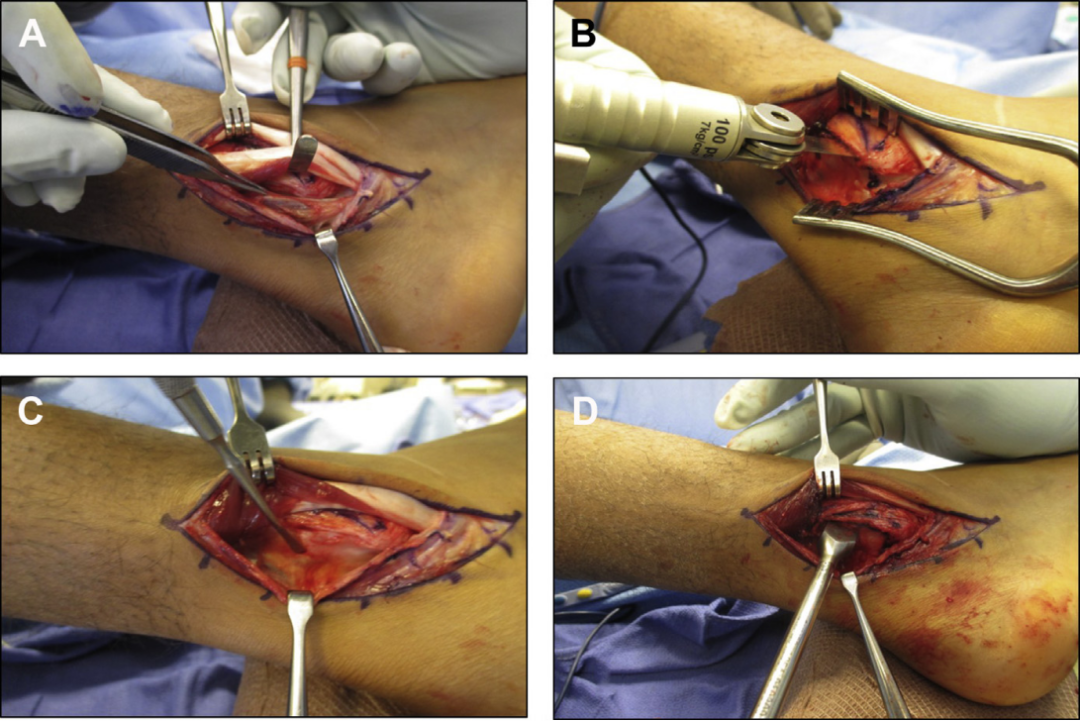

SPR撕脱开放手术锚钉修复

SPR撕脱关节镜手术锚钉修复

大部分急性损伤可以使用直接缝合修复,对慢性损伤则需根据患者的具体病理改变选择,如单纯的支持带结构损伤,可以直接缝合修复。如果直接修复不够稳定,需用其他组织加强。如果腓骨外踝窝较浅时,就需要使用加深手术。